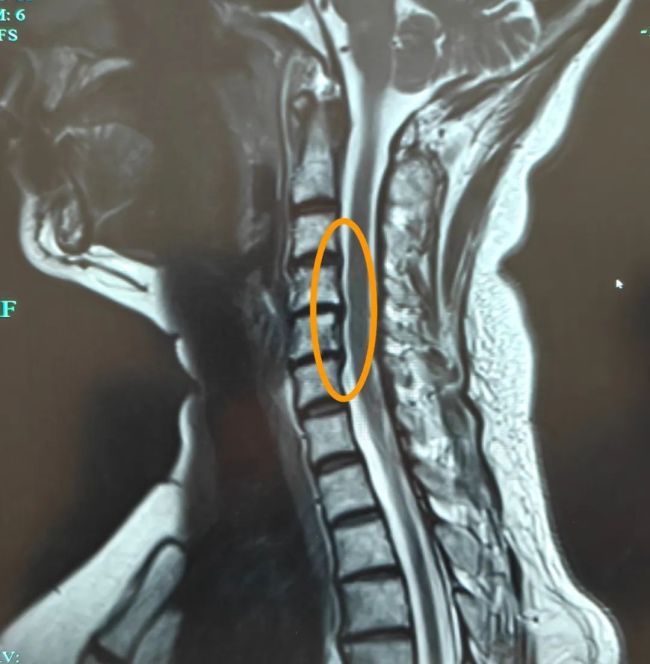

吕云按了按他的后枕部,患者立刻跳了起来:“就是这里!太疼了!真的受不了!”综合症状、体征及头颅CT结果,吕云诊断其为“伴颅周肌痛的颈源性头痛”。后续的颈椎磁共振检查也验证了她的结论:颈椎退变加椎间盘突出。吕云感叹道:“你这低头搓的哪里是麻将,是你‘颈椎的寿命’。”

这种头痛由颈椎病变引发,如退变或肌肉劳损,疼痛常放射至枕部和眼眶,易被误认为偏头痛或脑部疾病。典型特征包括单侧后脑勺胀痛,可蔓延至眼周和太阳穴;颈部僵硬,按压枕部肌肉有“扳机点”;长时间低头或伏案工作后加重,活动颈部可缓解。高危人群包括办公室白领、司机、手机“低头族”以及颈椎病患者。女性发病率是男性的2-4倍,与激素和肌肉张力有关。